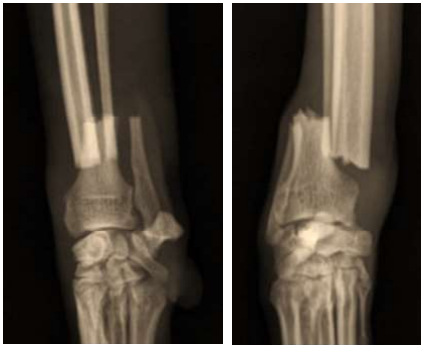

As radiografias abaixo pertencem a um Galgo Italiano, macho, com 5 anos de idade e 8 kg de peso corporal, que sofreu uma fratura fechada e não cominutiva do rádio ao saltar do colo do tutor:

A fratura será estabilizada com uma placa óssea de tamanho adequado. Considerando o tipo de fratura e as características do paciente, qual seria a função mais apropriada para a aplicação dessa placa?